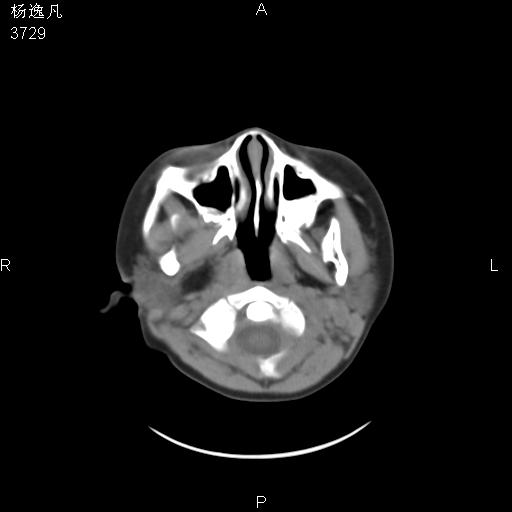

男性,5岁,面部受外伤,余无特殊

薄层

鼻咽顶后变窄。顶后壁增厚,考虑腺样体肥大。其它未异常/

1、右面部及颞部软组织肿胀。

2、腺样体肥大。

头颅ct平扫未见明确外伤性征象,右侧面部及颞部软组织肿胀,后鼻腔软组织影增大,增厚,鼻咽顶部变窄,考虑鼻咽腺样体增值肥厚。